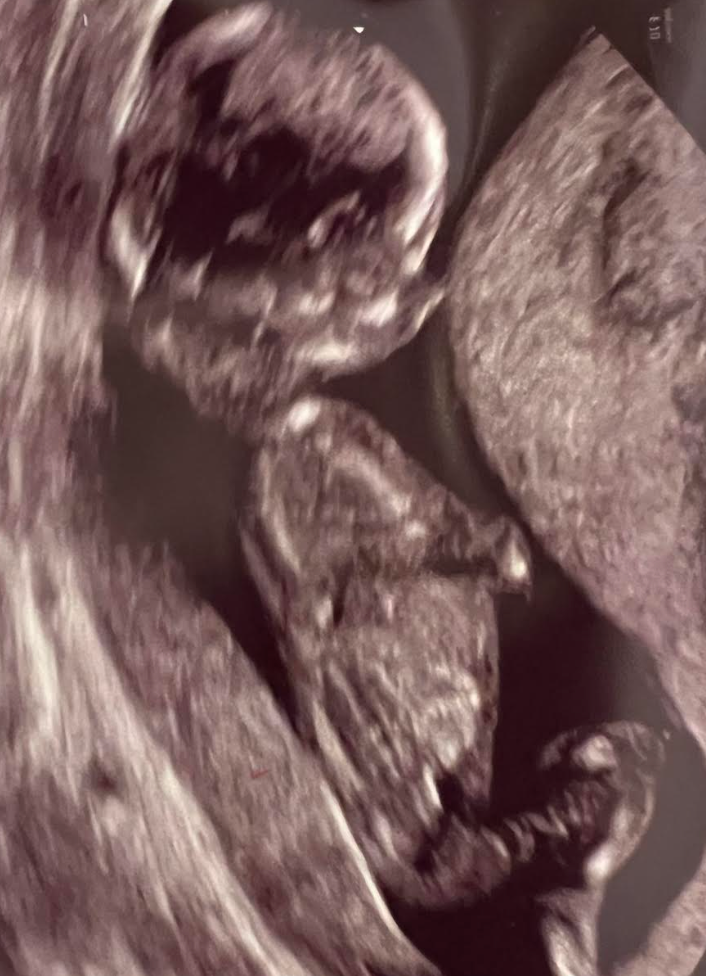

When I was 6 weeks pregnant, my husband, Ben, and I found ourselves in the harsh glow of our obstetrician’s office, anxiously awaiting the chance to get a glimpse of our little one on the ultrasound screen for the first time. She was barely the size of a lentil, but within that lentil was endless possibility — and also the potential for heartbreak.

Courtesy of Vaughan Bagley